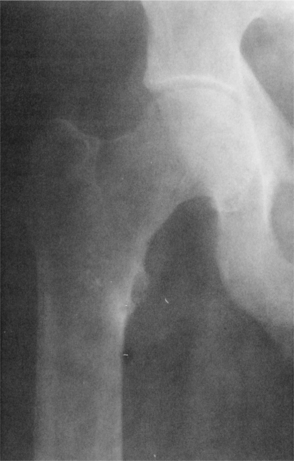

Demineralization results in an exaggeration of the osteoid seams seen radiographically adjacent to the relatively sparse areas of calcified bone (Fig. 24-6). As the osteoid accumulates, bone strength declines. These exaggerated seams occur because of the excessive time lag between collagen deposition and the appearance of the calcium salt. Areas of abundant osteoid appear radiographically as radiolucent stripes. These so-called pseudofractures, known as Looser’s zones, occur most commonly on the concave side of long bones, the ischial and pubic rami, and the ribs and scapula (Fig. 24-7). These pseudofractures develop from the healing of multiple microstress fractures in the moderately severe form of osteomalacia sometimes referred to as Milkman’s syndrome.107

Figure 24-6 Osteomalacia of the femur. Note the loss of the sharp interface between cortical bone and cancellous bone caused by demineralization of the cortex. (From Richardson JK, Iglarsh ZA: Clinical orthopaedic physical therapy, Philadelphia, 1994, WB Saunders.)

Figure 24-7 Osteomalacia. A, Forearm and B, femoral neck. Looser zones are seen as translucent zones with sclerotic margins. Usual sites include the medial femoral neck, pubic rami, lateral borders of the scapulae, and ribs. Complete fractures can extend through Looser’s zones; these will heal with appropriate treatment. (From Bullough P: Orthopaedic pathology, ed 3, London, 1997, Mosby-Wolfe.)

Radiographically, osteomalacia, like osteoporosis, may present as osteopenia. A bone biopsy may be done at the site of osteopenia to evaluate the bone matrix. Besides osteopenia, radiolucent bands in the bone cortex (Looser’s zones) may be revealed radiographically (see Fig. 24-7).